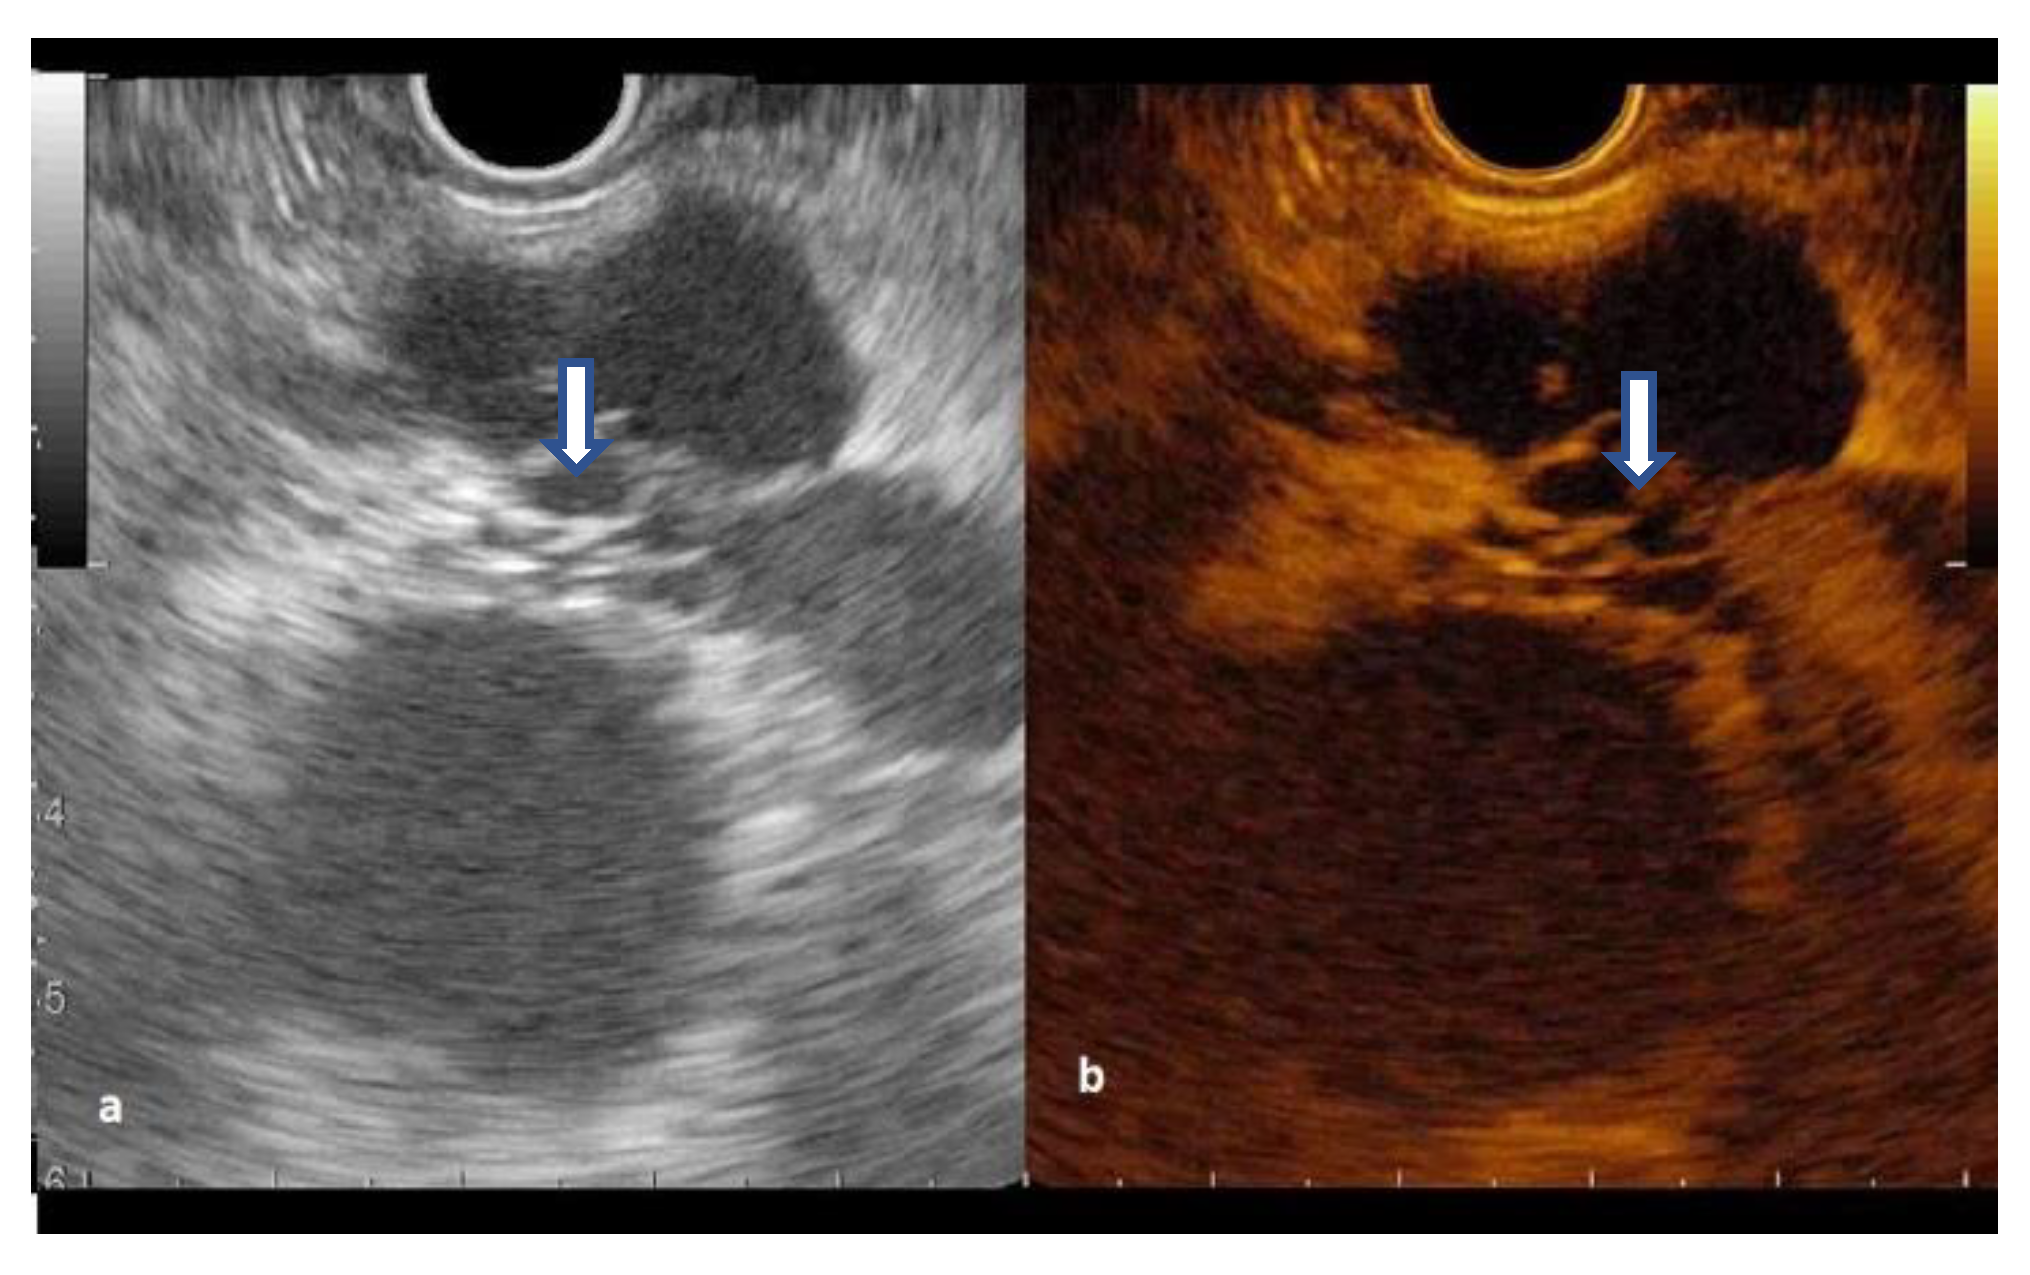

3.3. CH-EUS in Diagnosing Pancreatic Cysts

3.4. Contrast- EUS-FNA Assessment of Pancreatic Cysts